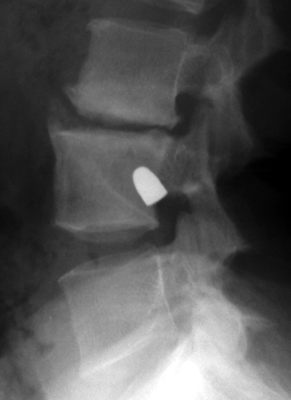

Tumbling Bullet Sign

Two sets of frontal and lateral radiographs, separated only by time, which reveal the "tumbling bullet sign"--which is simply a bullet which changes its location and orientation within a solitary bone cyst. This sign serves two purposes. It is documentation of the evolution of a solitary bone cyst as a corollary of trauma, and reveals the free movement of the foreign body within the confines of the lesion establishing its cystic rather than solid nature. It is similar to the fallen fragment sign.

- Click on the image for a larger versionA - Click on the image for a larger versionB - Click on the image for a larger versionC - Click on the image for a larger versionD